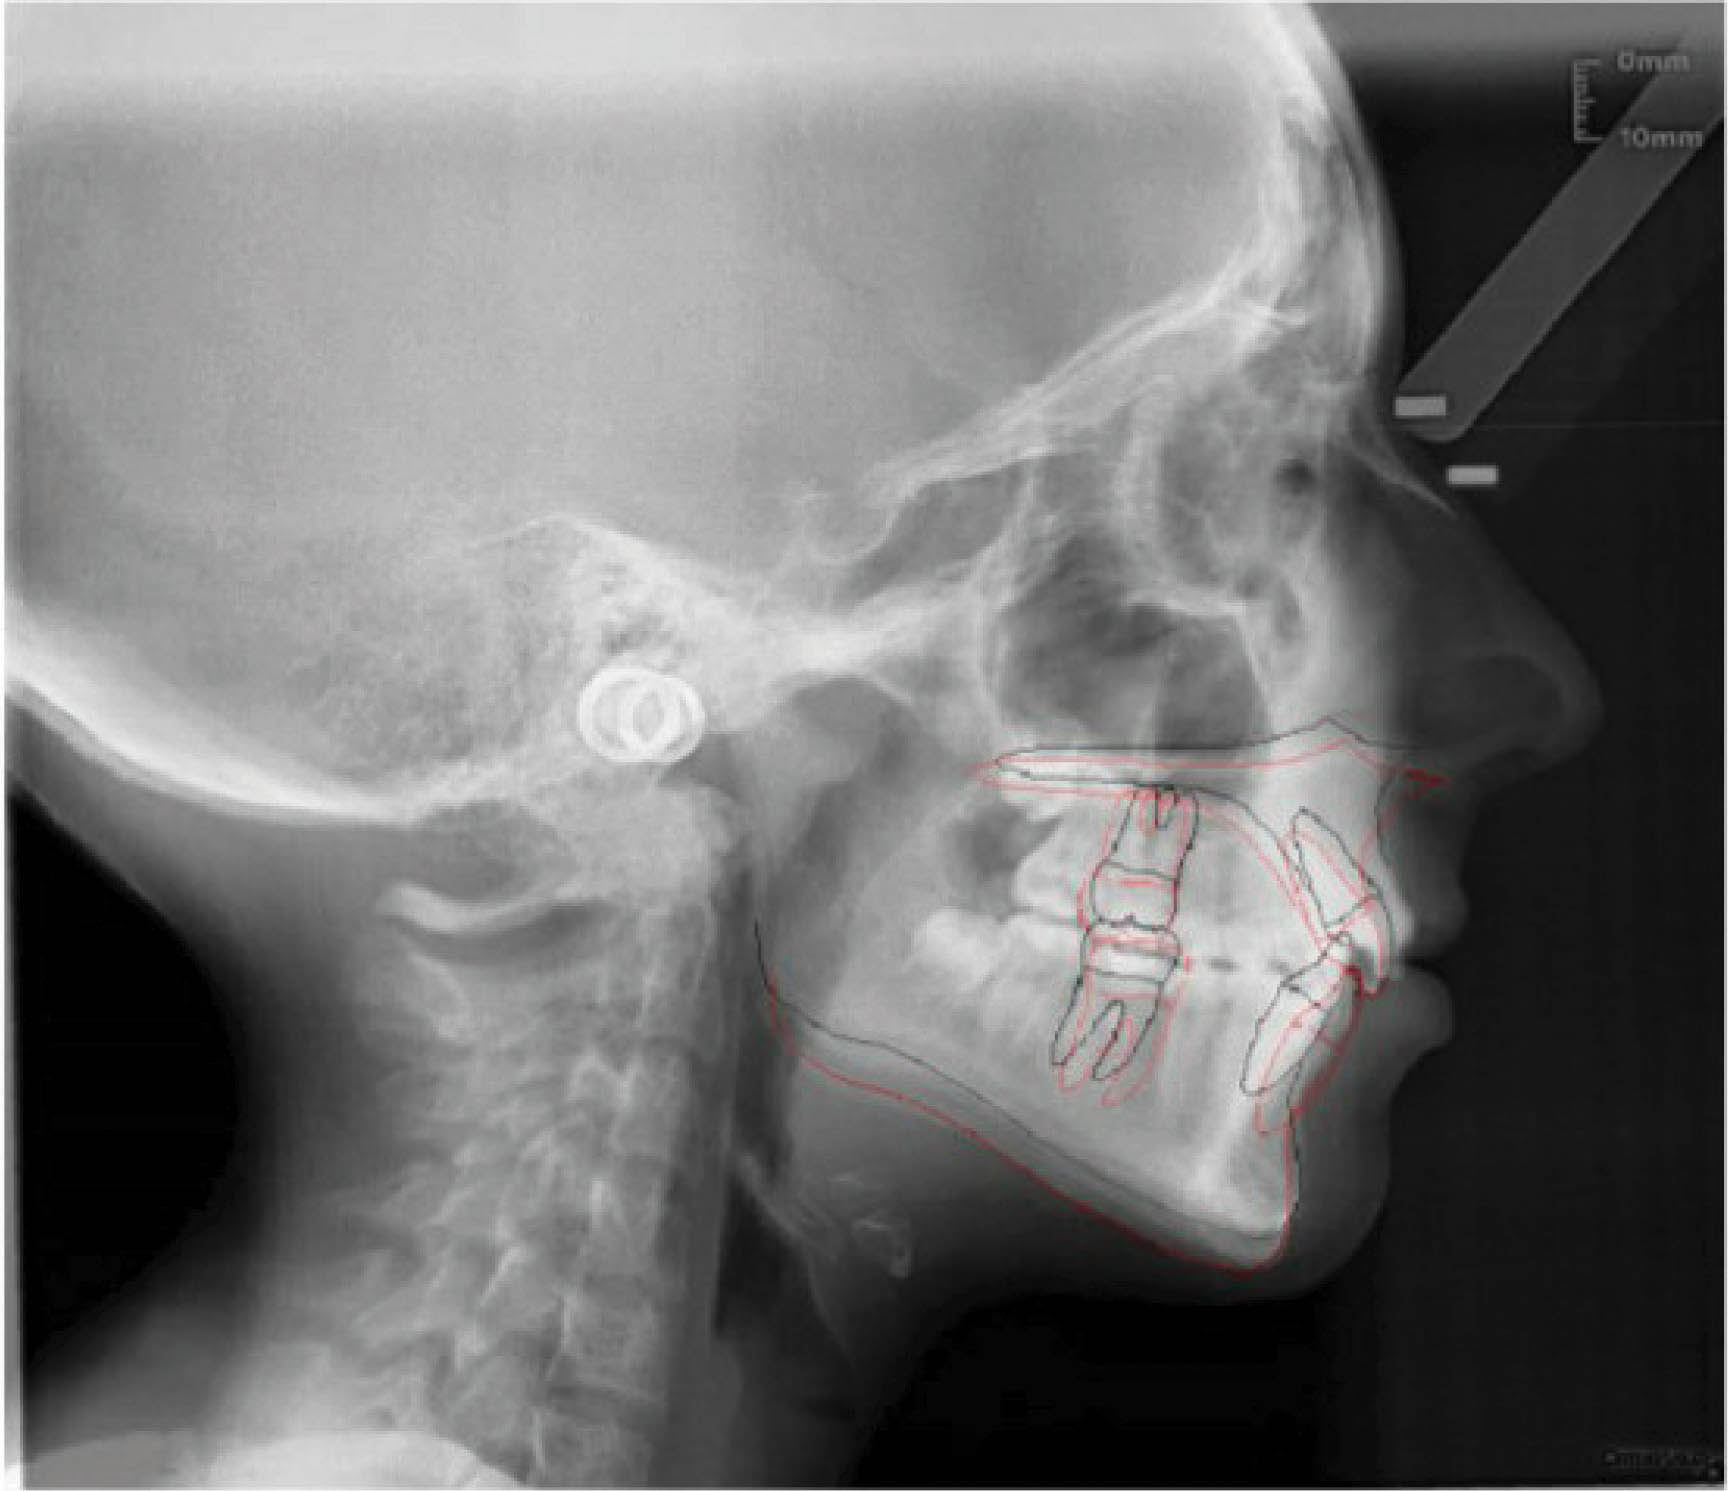

بیمار بعدی دختر ۱۲ ساله در مرحله اواخر میکس دنتیشن (شکلهای 92-۶ الی 94-۶) با اکلوژن ClII/1 است، دیپ بایت و کرادینگ دو فک دارد و لینگوالی شدن دندانهای قدامی بالا و پایین مشخص است. در (شکل 92-۶) هر دو لترال پایین را مشاهده میکنید که بلاک شدهاند. در OPG چیز خاصی مشاهده نمیشود و در لترال سفالومتری ارتفاع عمودی صورت کمی کاهش یافته و انسیزورها رترود شدهاند.

شکل 92-6

شکل 93-6

شکل 94-6

بخاطر در حال رشد بودن بیمار، استفاده از الاستیک کلاسII باعث اصلاح اکلوژن میشود. اصلاح کرادینگ با اکسپنشن خلف و پروترود نمودن قدام انجام میشود. اصلاح دیپ بایت به صورت نسبی و با پروترود شدن قدام انجام میگیرد.

نکته: چون دندان ۳ بالا هنوز کامل رویش نیافته بود، لذا روی ۴ بالا باتن درست گردید. کارایی الاستیک کلاسII چه از ۳ بالا و چه از ۴ بالا شروع شود خیلی فرقی نمیکند. مطالب مربوط به بُعد عمودی در صفحه 379 و مطالب مربوط به کرادینگ در صفحه 356 بیان شدهاند.

در انتهای درمان هم کرادینگ خوب درمان شد و هم رابطه مولری درست گردید (شکلهای 95-۶ الی 97-۶). عکس OPG طبیعی و سوپرایمپوز نمودن عکسهای لترال سفالومتری نشاندهنده پروترود شدن انسیزورهای بالا و پایین میباشد.

نکته: همانطور که در مقالات در اول مبحث بیان شد، موقعیت مولر بالا و نقطه A در طول درمان فرقی نمیکند. این تغییرات مانند استفاده از هدگیر است در حالیکه با الاستیک کلاسII بدست آوردهایم. ضمناً رشد مندیبل و قدامیتر قرار گرفتن نقطه پوگونیون هم مشخص میباشد و منجر به کاهش تحدب صورت گردیده است.

نتیجه: طول درمان ۲۸ ماه با دو قالبگیری مجدد و الاستیک کلاسII ۲ انسی بود.